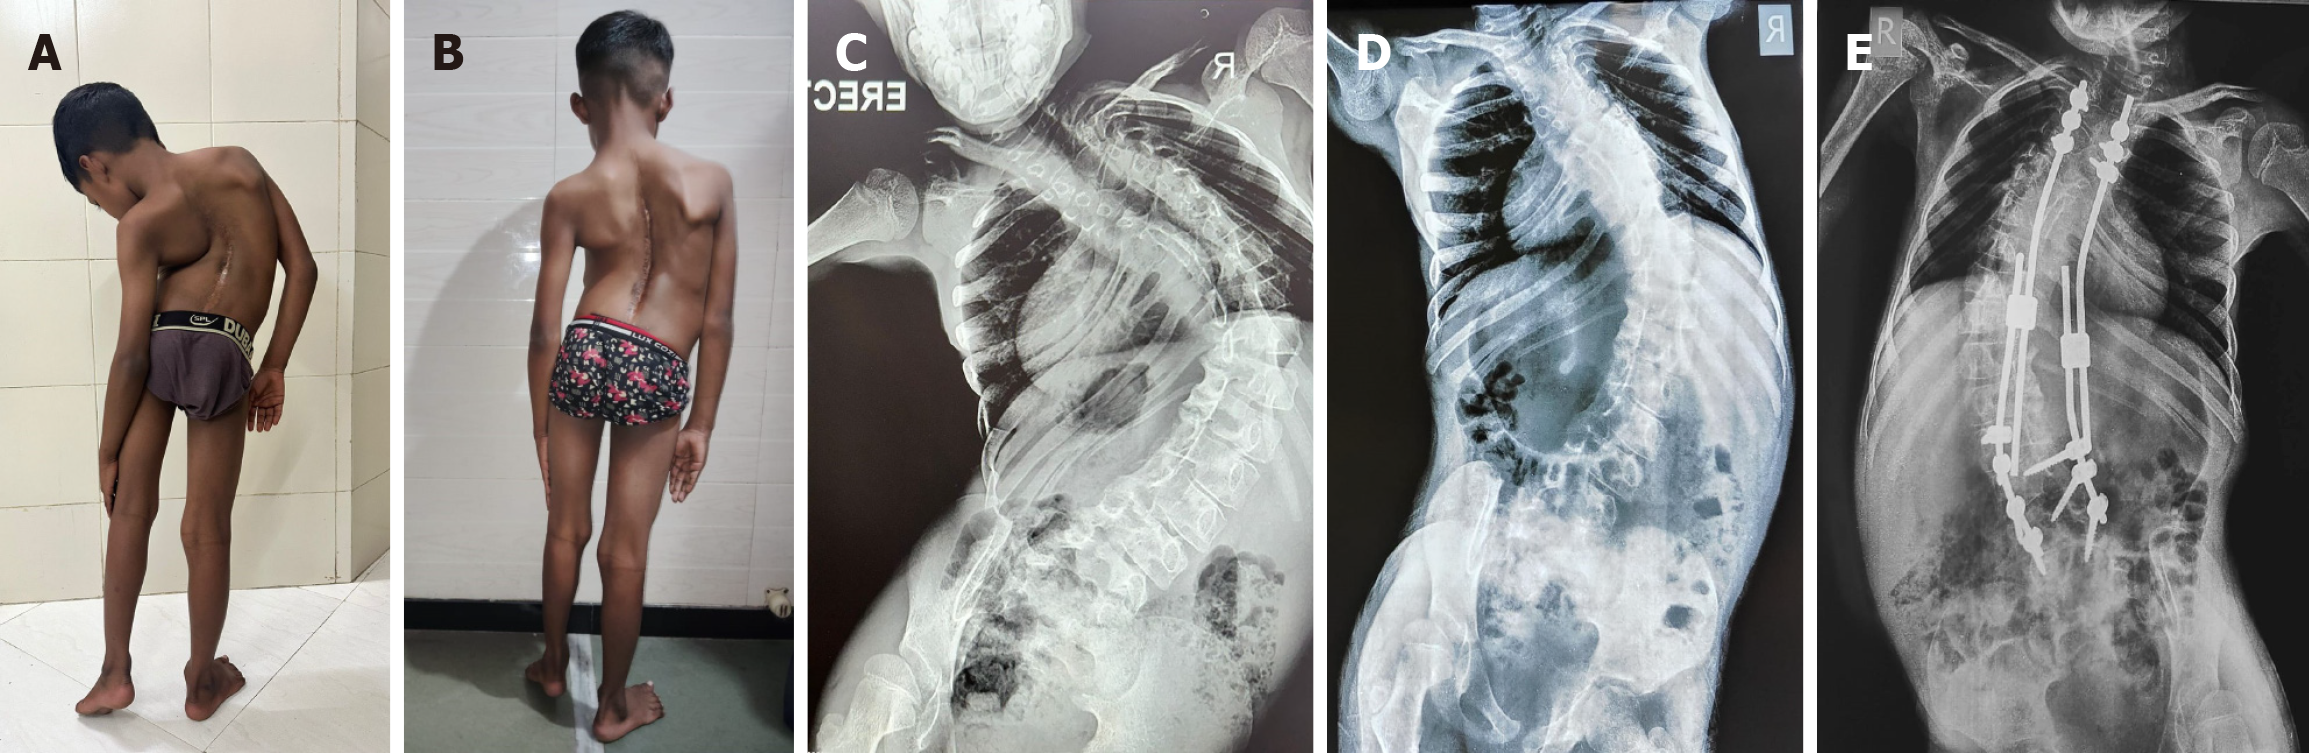

Figure 2 An illustrative example of severe scoliosis corrected with a staged procedure-halo gravity traction followed by posterior instrumentation and fusion.

A: Clinical picture of a 9-year-old boy, previously operated for diastematomyelia with severe thoracolumbar scoliosis with a decompensated curve; B: Clinical picture after application of halo gravity traction for 6 weeks and application of growing rods; C: Preoperative radiograph demonstrating scoliotic curve with a Cobb angle of 114°; D: Radiograph immediately before spinal instrumentation showing a Cobb angle of 76° (38° correction after halo gravity traction for 6 weeks); E: Postoperative radiograph with Cobb angle of 66 degrees after growing rod application.